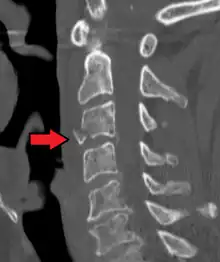

Radiographic detection

On CT scan or X-ray, a cervical fracture may be directly visualized. In addition, indirect signs of injury by the vertebral column are incongruities of the vertebral lines,[7] and/or increased thickness of the prevertebral space:[8]